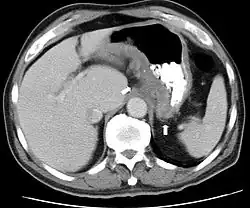

Rozpoznanie

- kolonoskopia połączona z pobraniem materiału do badania histopatologicznego

- wlew kontrastowy jelita grubego

- pasaż jelitowy

- badania laboratoryjne: podwyższenie OB, niedokrwistość, białko C-reaktywne – również do kontroli aktywności choroby[30]

- badanie w kierunku przeciwciał przeciw cytoplazmie neutrofilów i drożdżom Saccharomyces cerevisiae (ASCA, od ang. anti-Saccharomyces cerevisiae antibodies), pozwalające na rozpoznanie chorób zapalnych jelit[31] oraz różnicowanie z colitis ulcerosa[32]